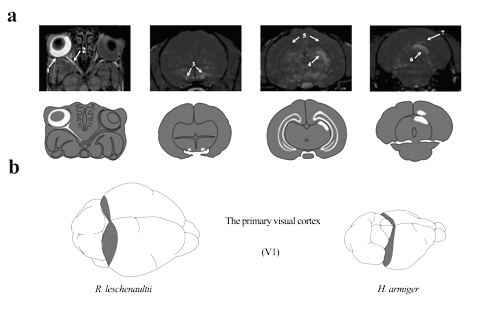

蝙蝠的视觉通路

大小蝙蝠上下丘体积比 昆明动物所供图

为进一步系统地揭示翼手目暗视觉适应性机制,张亚平课题组与胡新天研究员课题组、武汉物理与数学研究所徐富强研究员课题联合攻关,并在沈永义副研究员的带领下,博士研究生刘鹤群、魏景宽和李博首先利用锰离子增强磁共振成像(MEMRI)技术扫描蝙蝠大脑结构,对比各种蝙蝠视觉和听觉系统的结构差异,发现旧大陆果蝠具有较大的上丘(参与视觉信息处理),其上下丘体积比约3:1,食虫蝙蝠具有较大的下丘(参与听觉信息处理),其上下丘体积比约为1:7,揭示了翼手目动物暗视觉分化的脑结构基础。